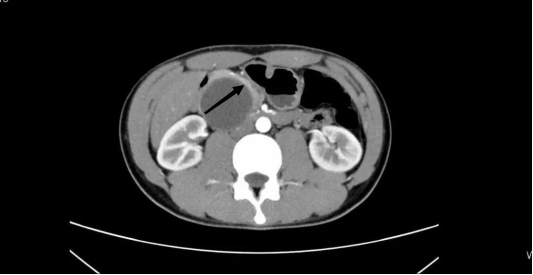

患者黄某,男,21岁,因中上腹痛3+天收入我院胰腺外科,入院前完善相关检查提示:胰头囊实性混合肿块影,最大截面约5.1*4.7cm,考虑实性假乳头状肿瘤可能,拟行腹腔镜下保留十二指肠的胰头切除术。

考虑患者年轻,且良性、低度恶性肿瘤预后良好,为降低手术创伤、保留更多器官功能,经过充分术前评估和准备,凭借团队丰富的手术经验,彭兵教授团队术中采取了改良的消化道重建方式:不离断空肠,将胰颈下拉至结肠下区,行导管对黏膜的直接吻合术,手术共耗时4个半小时,出血仅100ml,吻合耗时40分钟。术后第3天复查腹腔情况良好,术后顺利康复出院,无胰瘘、出血等相关并发症,生活质量良好,术后病理证实为:实性假乳头状肿瘤。